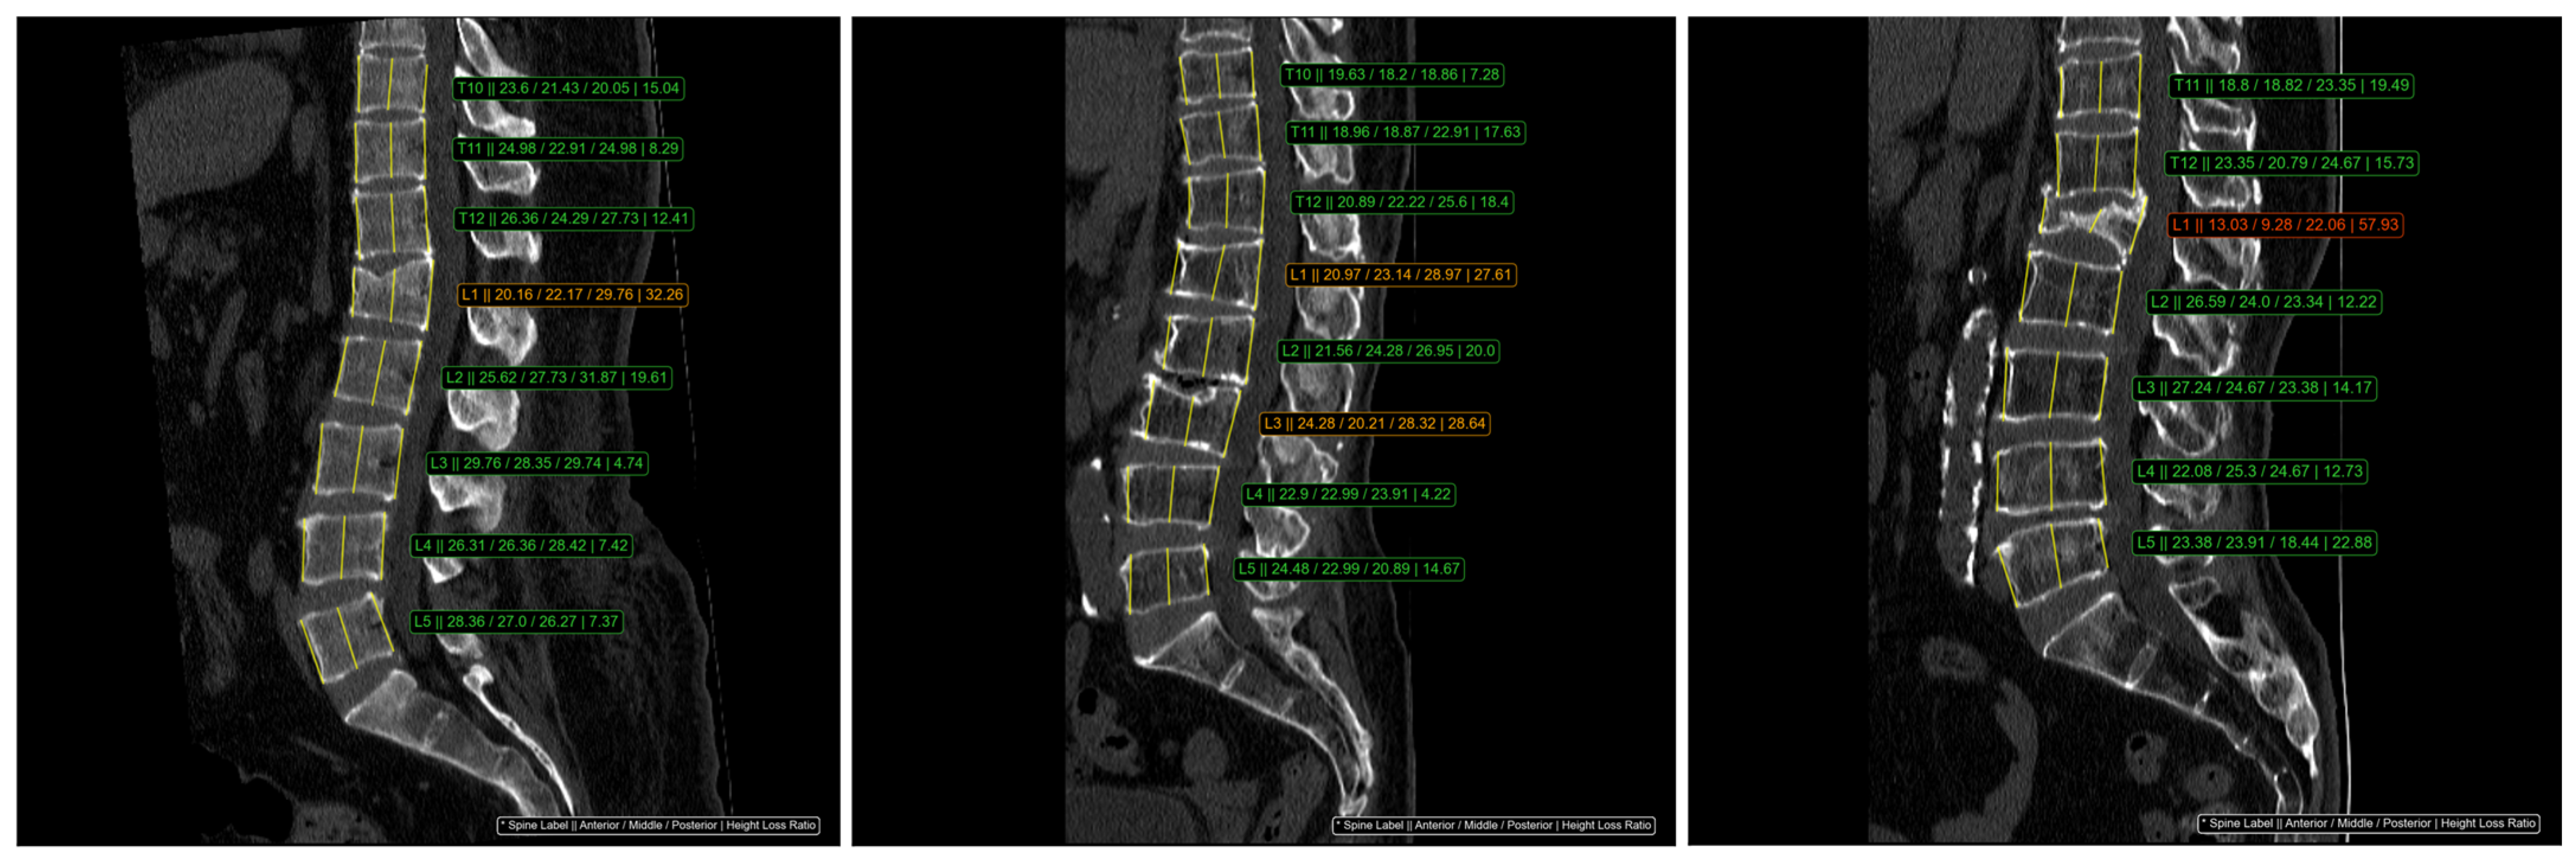

The Genant classification method was utilized to assess the height of three specific regions in each vertebral body. According to this system, vertebrae were classified into four categories: normal (HLR < 20%), mild compression (20% ≤ HLR < 25%), moderate compression (25% ≤ HLR < 40%), and severe compression (HLR ≥ 40%) [6]. The ClariVBA program automatically measured the height of the three regions for each vertebral body, calculated the height loss ratio, and provided quantitative values adjacent to each vertebra. Moderate fractures were displayed in orange, severe fractures in red, and mild fractures, which could exhibit inter- or intra-observer variation, were displayed in the same green color as normal vertebrae (Figure 1). In this study, vertebrae with mild compression were not classified as VCFs.

Figure 1. An example of automatic HLR measurement from DL-software, ClariVBA (Ver1.0, ClariPi Inc., Seoul, Republic of Korea). The consecutive values in the image, indicated with an * symbol, were spine label, anterior height, middle height, posterior height, and HLR. Moderate (Genant grade 2) VCF is orange and severe (Genant grade 3) VCF is red. The green color represented the normal vertebrae.